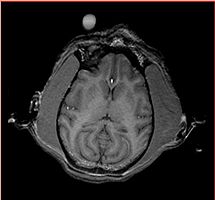

Gucci axial slice (#94) showing contrast for thalamus, globus pallidus, putamen

Same slice, template averaged from registered images

Same slice, template averaged from resampled images

Same slice, difference between 2 and 3